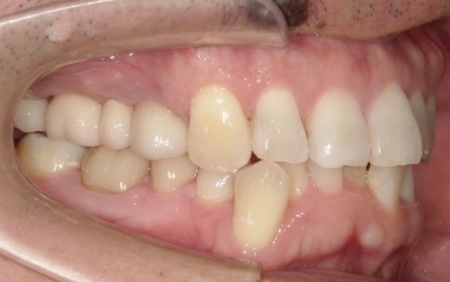

40代男性 温存が難しい複数の歯を抜いてインプラントブリッジで修復した症例

「ブリッジが外れたまま放置していた。また、前歯が欠けているのが気になる」とご相談いただきました。

拝見したところ、上左右の奥歯には、歯が失われていたり欠けたりしている部位が複数確認されました。

患者様によると、以前上顎にはブリッジ(両隣の歯を支えとして欠損部を補う装置)が装着されていましたが、10年前に外れたきりそのままの状態で過ごしていたとのことでした。

痛みがなかったため、とくに治療は受けていなかったようですが、以前から前歯の一部が欠けていることが気になっており、見た目や将来のお口の健康に不安を感じていたそうです。

そこで、詳しく検査を行った結果、欠けたり傷んだりしている歯が複数見つかり、さらに歯茎や歯を支える骨にも問題が生じていました。

とくに、右上奥歯は前から4番目と6番目の歯、左上奥歯は前から4番目・5番目・6番目・8番目の歯が著しく傷んでおり、温存が難しいと考えられます。

その一方で、上前歯や右下奥歯は、適切な処置を行うことで温存できる歯も複数確認できました。